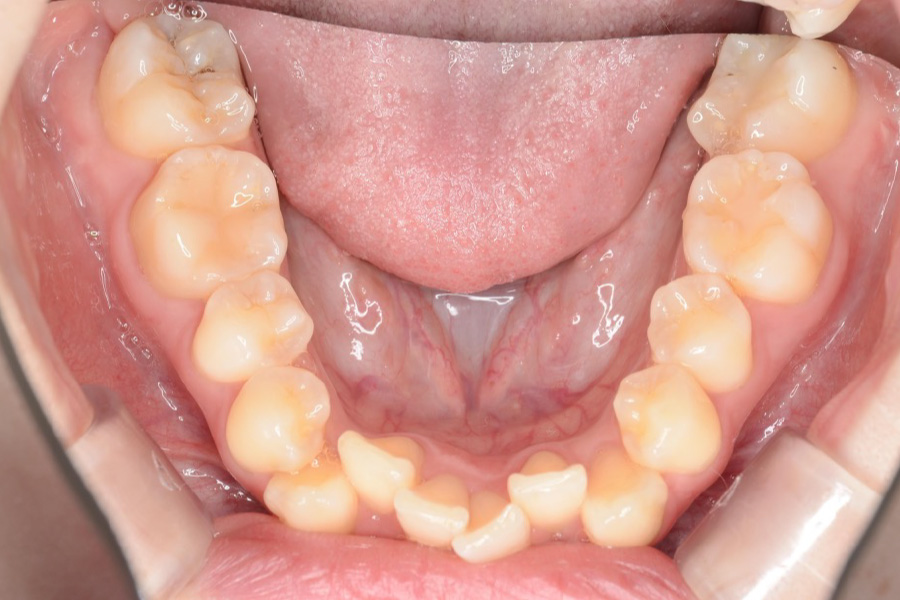

【20代女性】

全体のガタつきを

インビザライン矯正で治療したケース

治療後

主訴 全体のガタつきが気になる

治療内容 インビザライン矯正

小臼歯抜歯